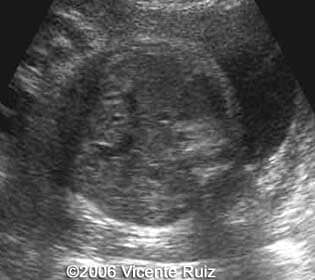

This is a 34-year-old-woman, G4P1A2, at 34 weeks gestation with a diaphragmatic hernia. The baby was born and died immediately. The autopsy confirmed the diaphragmatic hernia. The left hemithorax was occupied by abdominal organs as stomach, colon, appendix, left hepatic lobe, spleen. A karyotype was performed with an abnormal result (45, X0). A Turner"s syndrome was the final diagnosis.

Axial views of the chest showing the left hemithorax occupied by an heterogeneous mass

Note the stomach into the left hemithorax

Note the absence of the stomach in the axial section of the abdomen